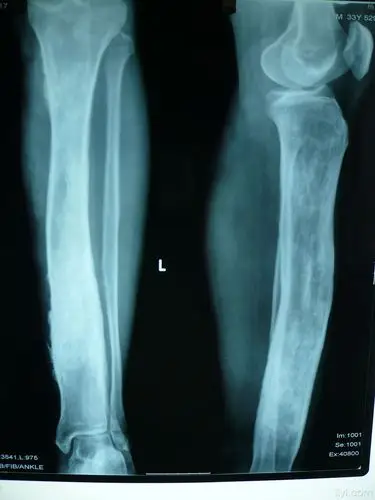

这一例胫骨慢性骨髓炎大家有啥好建议

慢性骨髓炎伴骨外漏

慢性骨髓炎讨论